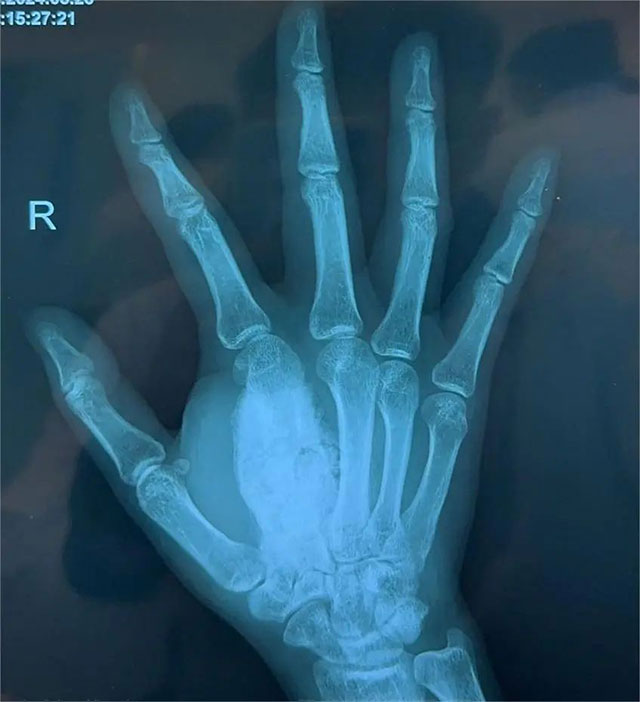

右手斜位